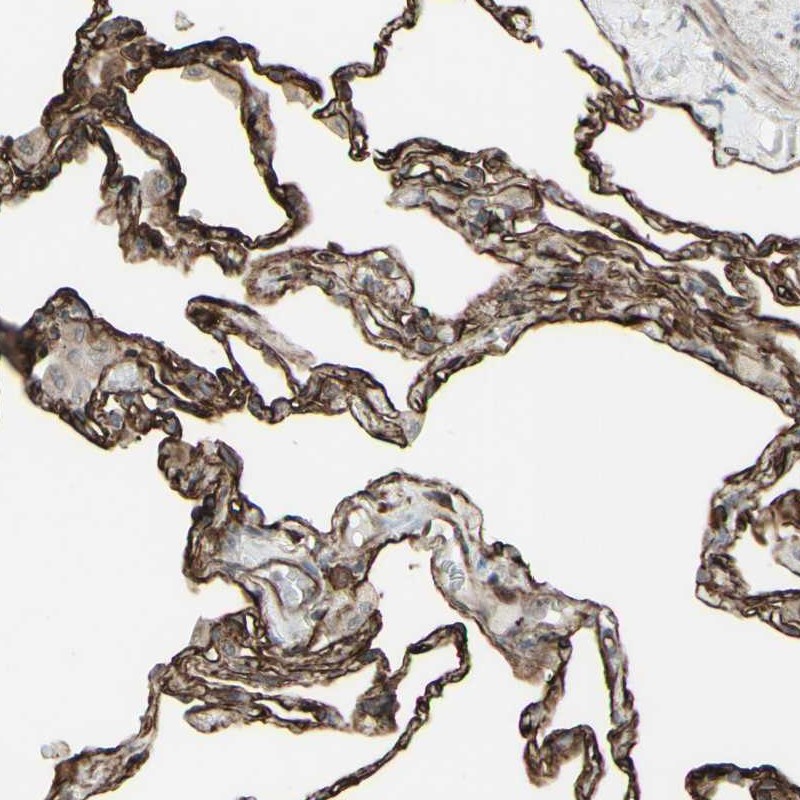

Immunohistochemical staining of human lung shows strong cytoplasmic and membranous positivity in alveolar cells.